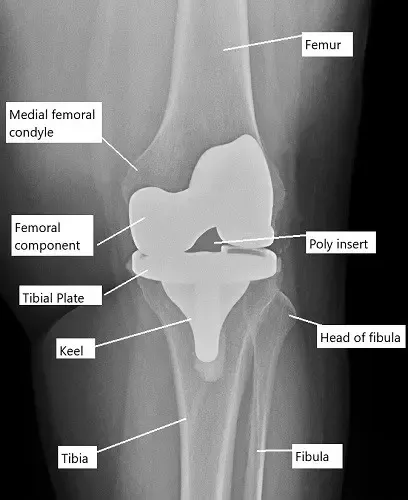

La articulación de la rodilla es una articulación articulada de bisagra formada por el fémur (hueso del muslo), la tibia (hueso de la espinilla) y la rótula (rótula). El fémur y la tibia están cubiertos con cartílago articular para permitir un movimiento suave, y la rótula se desliza sobre la superficie femoral. La cirugía de reemplazo de rodilla consiste en retirar las partes dañadas de estos huesos y reemplazarlas por componentes protésicos. Estos componentes protésicos se fijan con cemento óseo (cementados) o se insertan a presión en el hueso (sin cemento), y restauran la función y movilidad de la articulación de la rodilla.

Radiografía que muestra un reemplazo total de rodilla.